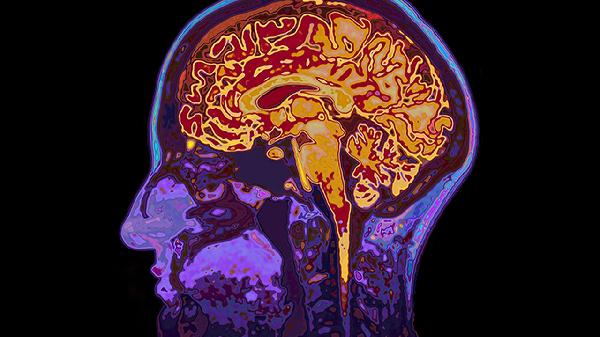

突发单侧上肢或下肢无力是脑血栓的典型前兆,可能与大脑中动脉供血区缺血有关。患者常表现为持物不稳、行走拖沓,严重时可能出现偏瘫。此类症状多由动脉斑块脱落堵塞血管导致,需通过头颅CT或MRI确诊。急性期可遵医嘱使用阿替普酶注射液进行静脉溶栓,恢复期可服用阿司匹林肠溶片预防复发,同时配合血塞通软胶囊改善脑循环。